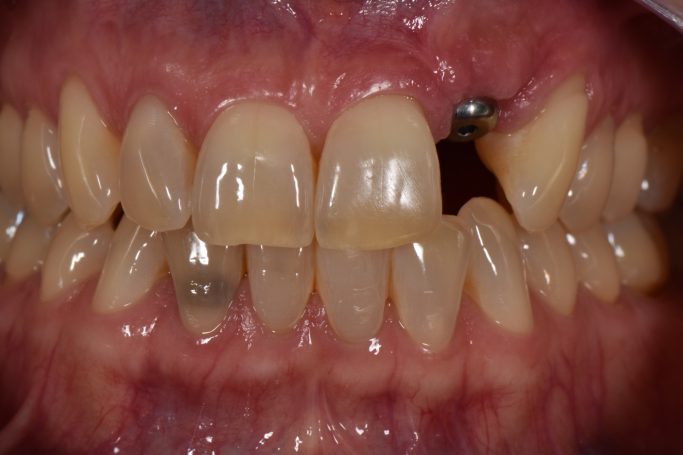

Teleskopierende Oberkieferbrücke mit Vorher- und Nachher-Situation des Patienten.

Teleskopierende Oberkieferbrücke. Wie die eigenen Zähne, aber einfach zu reinigen.